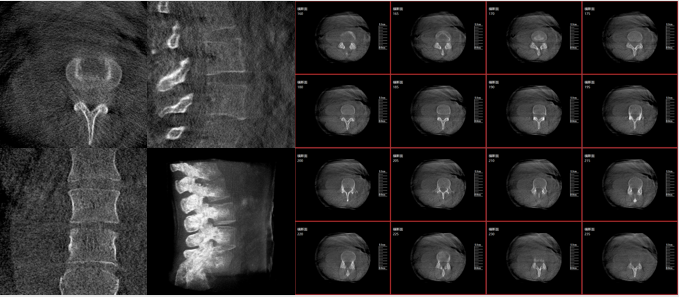

術中三維影像

而三維影像的MPR圖像組可以通過不同平面的切分,使成像區內更豐富的信息得以呈現。尤其是二維影像無法涉及的橫斷面,提供了另一個空間維度的信息量。

作為使用者,醫生在手術中雖然有術前的影像作為判定依據,但每一臺手術都具有獨特性,需要術中三維影像提供的實時信息,作為術中診療操作的基礎。

二、準確的手術效果判定

在MPR圖像中,冠狀面、矢狀面和橫斷面的信息大大提高了醫生對于病灶區以及手術效果的判定。